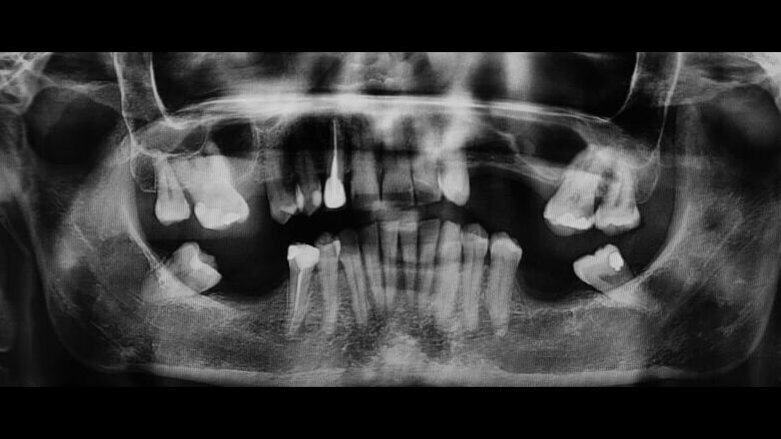

In questo case report è stata selezionata una paziente di sesso femminile, S.P. (54), non fumatrice, con buona igiene orale e con anamnesi negativa all’assunzione di farmaci, ad allergie, disturbi metabolici e patologie sistemiche (Figg. 1-3). È stata proposta una tecnica di rialzo del seno mascellare eseguita mediante strumenti piezoelettrici (Piezosurgery®, Mectron, Genova, Italy) (Figg. 9, 10, 13).

In seguito all’intervento di rialzo di seno mascellare con contestuale GBR è stata eseguita la radiografia ortopanoramica che mostra il corretto riempimento dell’area atrofica del seno mascellare con granuli cortico-spongiosi di osso di origine bovina. Al controllo dopo tre settimane i tessuti molli dell’area trattata risultano perfettamente guariti. La TC Dentalscan effettuata dopo 6 mesi per il controllo della zona rigenerata evidenzia la perfetta guarigione della zona con aumento dello spessore osseo di 5 mm e dell’altezza ossea di 11 mm.